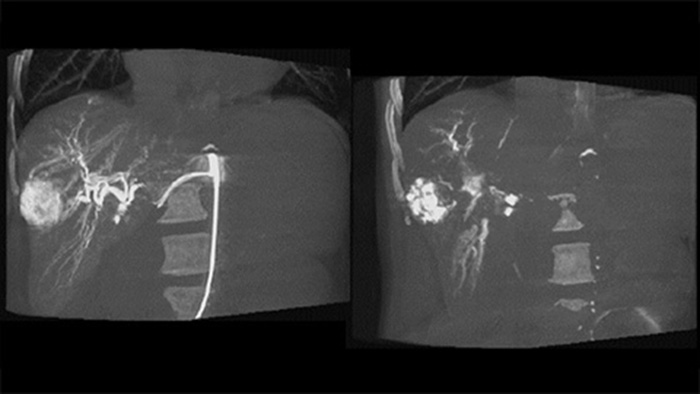

CBCT Dual enables 3D acquisition of an arterial phase to visualise vascular structures and a post-arterial (delayed phase) to visualise accumulation of contrast medium, in a single automatic step.5

Dual View allows simultaneous visualisation of two CBCT datasets. Both arterial and delayed phase can be displayed next to each other or in a single fused overlay view.